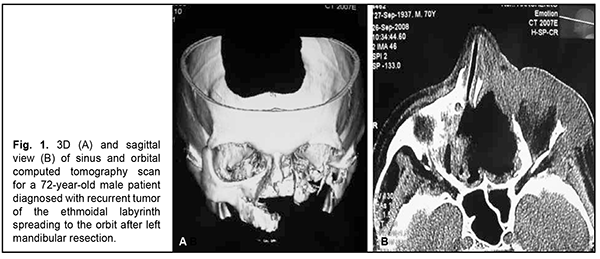

Introduction Cancer incidence is on the rise globally. In Ukraine, 160 thousand people (0.32% of the population) are diagnosed with cancer every year, and there are 100 thousand deaths [1, 2, 3]. By comparison, out of the total US population of 247 million, 50 thousand people (0.02% of the population) are diagnosed with cancer every year [1, 3, 4]. Therefore, cancer is a major medical and social problem both globally and within Ukraine. Diagnosing malignant tumors of the ethmoidal labyrinth early, with advanced techniques, is important, because late diagnosis may lead to intracranial spread to the eye or base of the skull (sinus sphenoidalis), making radical and organ-preserving surgical treatment difficult and, consequently, worsening the patient’s quality of life [1, 4, 5, 6]. When the tumor of the ethmoidal labyrinth expands to the eye, orbital tissues of the inner, superior and orbit and the orbital apex are most commonly affected, with the disease spread to the ocular adnexa (the medial angle of the eye and eyelids). It is not uncommon that the eye globe is involved into the tumor process [1, 4, 5]. The mechanism of spread of the tumor of the ethmoidal labyrinth to the orbit is implemented particularly via easy erosion of the lamina papyracea (a thin bone separating the orbital cavity from the ethmoid sinuses), with lesions affecting the orbital tissues, eye globe and ocular adnexa. In other cases the malignant tumor erodes the orbital floor. Therefore, for these cases, the surgical treatment involves exenteration of the orbit and sinus, an extended mutilating surgical procedure. The success rate of this surgical procedure in the presence of spread of the tumor of the ethmoidal labyrinth to the orbit has been reported to exceed 60% [5, 6]. Late presentation for medical care and patient’s denial of surgical treatment in the presence of an initial or limited cancer lesion are the major causes of the expansion of a malignant process and lack of efficacy of radical treatment. Thus, our previous studies have indicated that more than half of patients with tumors of the ethmoidal labyrinth presented with T3 or T4 tumor stage [1, 4]. The purpose of the study was to assess the efficacy of exenteration of the orbit and sinus in the presence of the tumor of the ethmoidal labyrinth spreading to the eye. Material and Methods Sixty-two patients with a malignant tumor of the ethmoidal labyrinth spreading to the eye received surgery at the Head and Neck Department at Odesa Municipal Clinical Hospital No. 11 during 2017 through 2022. Of these, 42 (75.8%) were females and 20 (32.2%) were males, with patient age ranging from 55 to 75 years. The primary tumor was located in the ethmoidal labyrinth in all these patients. They underwent general clinical tests, rhinoscopy of the nasal cavity, and computed tomography (CT) of the paranasal sinuses and orbit. In addition, an eye cancer specialist from the Filatov institute examined and evaluated the status of the eye to make a common decision on the extent of surgery. A preoperative biopsy was obtained from the nasal cavity tumor after anesthesia with 10% lidocaine and sent for histological examination. Forty five patients received surgery for a primary tumor of the ethmoidal labyrinth spreading to the orbit, and 17 patients, for tumor regrowth after subtotal or partial removal of a primary maxillary sinus tumor that had spread to the maxilla. Patients were proposed to undergo an exenteration of the orbit and sinus, a radical surgical procedure, due to the size of the ethmoidal labyrinth lesion invading the orbital and optic nerve, with the development of optic nerve atrophy leading to a total loss of vision; informed consent for surgery was obtained from all patients. One month after surgery, patients received preventive radiotherapy, with a dose of 40-45 Gy applied to the bed of the primary tumor. Surgery efficacy was assessed by early postoperative results (particularly, the type of postoperative cavity healing and the presence or absence of complications like purulent inflammation) and late postoperative results (particularly, the presence or absence of tumor recurrence or regrowth after subtotal or partial removal, metastatic process development) and patient’s quality of life. All patients were treated postoperatively with topical and systemic anti-inflammatory and anti-bacterial therapy (sea-buckthorn oil dressings). At day 12 after surgery, patients were discharged for outpatient treatment and follow-up. By the time of patient discharge, postoperative nasal and orbital cavities were clear and filled with granulation tissue. Patients were recommended to have furacylin ointment dressings applied to their wounds until complete epithelialization occurred. The minimum follow-up duration was 3 years, but a patient may have a life-long follow-up if requested by the patient. In addition, a patient should be followed up by an oncologist at the place of residence. Results All the 62 patients (100%) complained of difficulty with nasal breathing on the affected side, periodic nasal bleeding, loss of vision and exophthalmos. Thirty two patients (51.6%) exhibited soft tissue edema around the eye, conjunctival chemosis, difficulty with reposition of the eye, and partial or total ophthalmoplegia. Ethmoidal labyrinth and ocular lesions were more common on the left than on the right side. There was CT evidence of tumor of the ethmoidal labyrinth spreading to the orbit in all the patients (100%). Based on histological examination of tumor biopsy and postoperative material, all patients had a moderately differentiated (G2) tumor. The exenteration of the orbit and sinus had no complications (i.e., there was moderate bleeding), and the tumor was removed radically in all patients. In 40 patients (64.5%) with the tumor spread to the temporal cell tissue, the extent of surgery was expanded to include a block of affected tissues from this region. It is noteworthy that a postoperative course was satisfactory and showed no complications like purulent inflammation in all patients. Postoperative wound healing was characterized by gradual granulation tissue formation and re-epithelialization of the bone surface. No recurrence or metastatic process development was observed over a follow-up period of three years. The assessment of quality of life after exenteration of the orbit and sinus, an extended mutilating surgical procedure, showed that patients experienced stress due to a gross cosmetic defect and loss of the eye and, consequently, required psychological consultation and care, which was offered and provided on request to all patients. Figure 1 (a, b) shows CT scans of a patient with a tumor of the ethmoidal labyrinth spreading to the orbit. A 72-year-old male patient underwent a radical left maxillary sinus surgery and left maxillary resection. Nineteen months thereafter, he was diagnosed with a tumor of the ethmoidal labyrinth spreading to the orbit. After the patient underwent a complete examination and was consulted by an eye cancer specialist, he agreed to have his orbit contents removed and all his paranasal sinuses revised (Fig. 2).